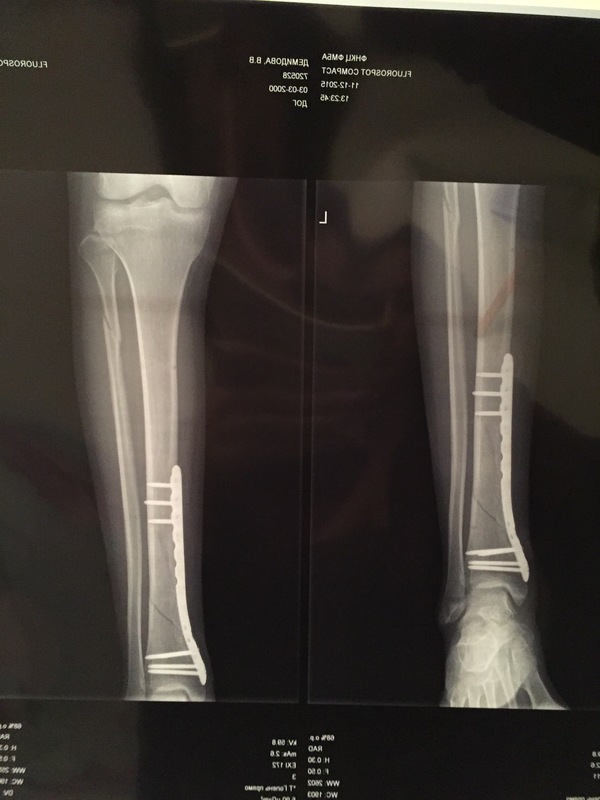

Сделали операцию.В больнице я пролежала месяц,поэтому про больницу могу рассказать многое.На данный момент я прохожу лечение.И вся эта ситуация дала отличную возможность спокойно подготовиться к экзаменам.

А нога на данный момент внутри выглядит вот так

До сих пор меня не покидает та мысль,что доктора в госпитале не знали что в нижней трети голени кровоснабжение минимальное.Выводы делайте сами о медицине,может это мне доктор попался такой,но не все,что есть заграницей лучше,чем в России.